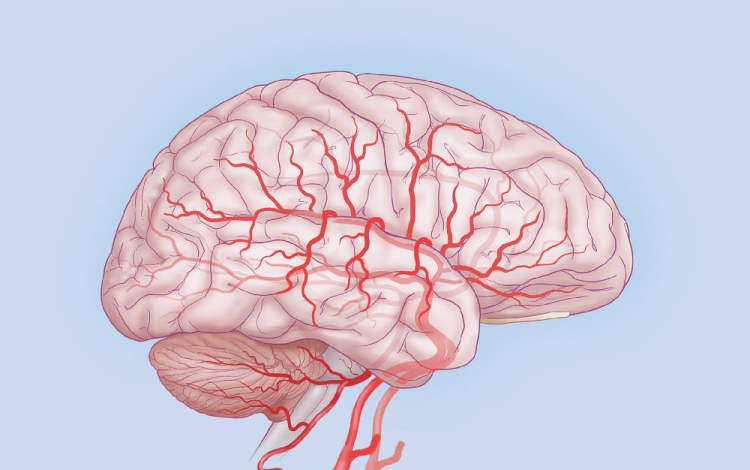

A Stanford Egyetem kutatói rohamok során jelentkező agyi aktivitást konvertáltak zenévé.

Dr. Josef Parvizi neurológus és Chris Chafe professzor, zenekutató mintegy száz elektróda segítségével regisztrálta a rohamok során keletkező agyi aktivitást, és a mintázatot zenévé alakították át. Az egyes hullámokhoz az emberi hangtartományhoz közeli hangjegyeket rendelve jutottak el az agy zenéjéig.

A módszer során a hagyományos módszert jelentő eeg-vel térképezték fel a normál aktivitás, illetve a görcsroham során jelentkező elektromos hullámokat, melyek az idegsejtek kisülése miatt jönnek létre.

A módszer jelentősége túlmutathat egy érdekes kutatáson, ugyanis az így kapott hallgatózási lelet alapján könnyűszerrel el lehet különíteni a rohamos aktivitást a normál működésre jellemzőtől. A kutatók szerint az „agyi sztetoszkóp” az epilepsziás betegek diagnosztikájában jelent pontosabb alternatívát. A fejlesztés az egyetem Bio-X Interdiszciplináris Programjának keretein belül zajlott, mely 2000 óta fut, és mintegy 141 tudóst foglalkoztat.